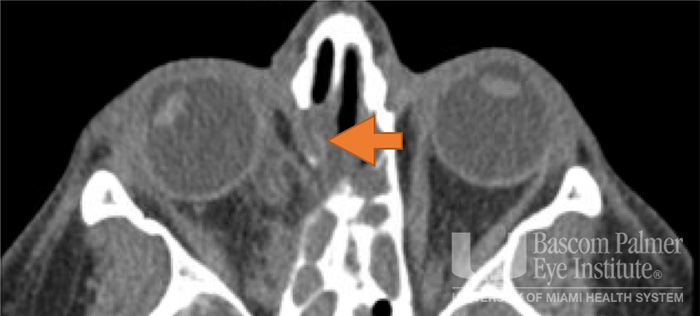

Paralytic and restrictive medial rectus dysfunction secondary to cocaine-induced midline destructive lesions.